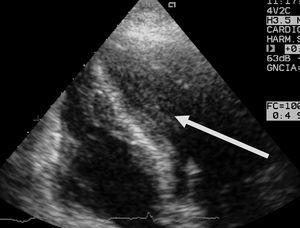

Aparte de la heterogeneidad de las distintas descripciones, de todos los estudios publicados se desprende que en presencia de patología neurológica grave se puede producir una disfunción miocárdica con una incidencia desconocida, pero que podría estar en torno al 9%, que mejora habitualmente en la primera semana, y es reversible en la mayoría de los supervivientes entre el primer y el sexto mes. Aunque la causa del fallecimiento es dependiente de la propia patología cerebral, dicha disfunción miocárdica reversible puede contribuir a la mortalidad, o al menos incrementar la morbilidad al poder cursar con complicaciones tales como arritmias potencialmente letales15,29, hipotensión arterial, edema pulmonar15,29, hipoxemia13-21, que podrían potenciar las lesiones cerebrales secundarias, así como formación de trombos intracavitarios en el ventrículo izquierdo12,14,15,18 que podrían provocar embolias15 (fig. 2). Por otra parte, esta disfunción miocárdica puede ser una causa directa del edema neurogénico o al menos contribuir a su desarrollo, ya sea por la propia disfunción ventricular sistólica o por otras complicaciones asociadas, tales como una insuficiencia mitral grave (figs. 3 y 4).

Figura 2. Ecocardiografía transtorácica, plano apical 4 cámaras, donde puede observarse una imagen de trombo y ecocontraste espontáneo en el ventrículo izquierdo de un paciente de 21 años con hemorragia subaracnoidea e hipoquinesia ventricular izquierda global grave.